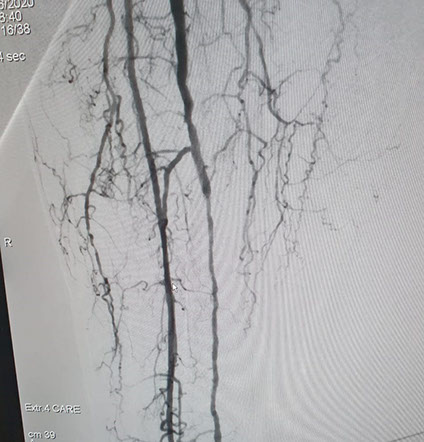

El Dr Sergio Raul Ludueña Jefe del Servicio de Hemodinamia de INCOR nos comentó sobre procedimiento realizado en el día de ayer en en el Servicio. "Queremos compartir con ustedes si bien no es un caso coronario , es un paciente obeso mórbido, diabético, con amputación supracondilea de miembro inferior izquierdo hace 3 años y actualmente con isquemia critica de miembro inferior derecho, con oclusión de ambas tíbiales y sin circulación en el pie".

Se realizó un abordaje híbrido con el Dr. Alejandro Flores, y se re canalizó ambas arterias tíbiales. Procedimiento inédito en nuestra provincia.

Las imágenes siguientes son previas al procedimiento y posterior se ve ambas arterias tíbiales permeables, y circulación en el pie